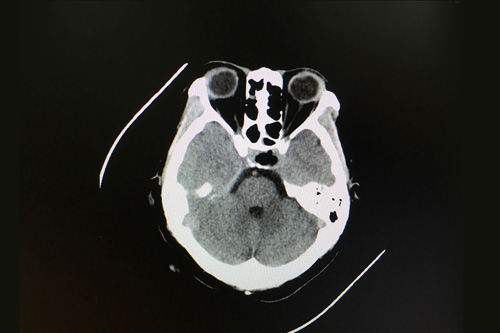

術(shù)前影像顯示:垂體占位,不排除垂體瘤囊性變

這時(shí),從患者影像資料上來看,顱內(nèi)鞍區(qū)的腫物大小為1.3cm*2cm*0.8cm,可以確認(rèn)是鞍區(qū)良性腫瘤,垂體瘤囊變的可能性較大,有壓迫視神經(jīng)的跡象。性激素檢查發(fā)現(xiàn)患者垂體泌乳素分泌很高,超出參考值范圍55個(gè)單位。占位引起高顱壓,壓迫神經(jīng),造成患者額頭和兩側(cè)顳部疼痛明顯,眼睛也出現(xiàn)脹痛癥狀,已嚴(yán)重影響到其生活。各位專家會診結(jié)果:垂體瘤囊變符合手術(shù)指征,應(yīng)盡快安排手術(shù)。做了手術(shù)會盡快解除壓迫,垂體激素分泌也會逐步回歸正常。

患者術(shù)后影像:鞍區(qū)腫瘤術(shù)后改變,腦內(nèi)未見明顯異常